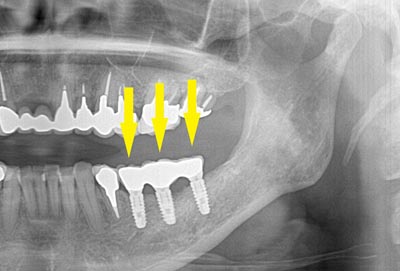

インプラントを埋入するためには、骨を増やさなければならず、患者様ご自身の骨を移植する、自家骨移植術を行なうこととしました。写真、青色の矢印で示す、智歯周辺の骨を採取し、黄色の矢印の部位に骨片を移植、チタン製の小さなスクリューで骨片を固定するという手術を行いました。細く、白く映っているのが骨を固定したミニスクリューです。

インプラントを埋入するためには、骨を増やさなければならず、患者様ご自身の骨を移植する、自家骨移植術を行なうこととしました。写真、青色の矢印で示す、智歯周辺の骨を採取し、黄色の矢印の部位に骨片を移植、チタン製の小さなスクリューで骨片を固定するという手術を行いました。細く、白く映っているのが骨を固定したミニスクリューです。